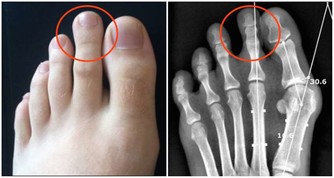

4、鈣片+菠菜

菠菜中含有大量草酸鉀,進入人體後電解出的草酸根離子會沉澱鈣離子,不僅妨礙人體吸收鈣,還容易生成草酸鈣結石。專家建議服用鈣片前後2小時內,不要進食菠菜,或先將菠菜煮一下,待草酸鉀溶解於水,將水倒掉後再食用。